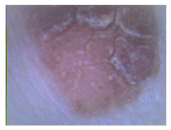

The results obtained after the first stage of image processing are presented in Figure 10.

Figure 10.

The results after the first stage of image processing: (a) image for analysis, (b) image after the median filter, (c) image after morphological operations, (d) image after improvement of brightness and contrast.